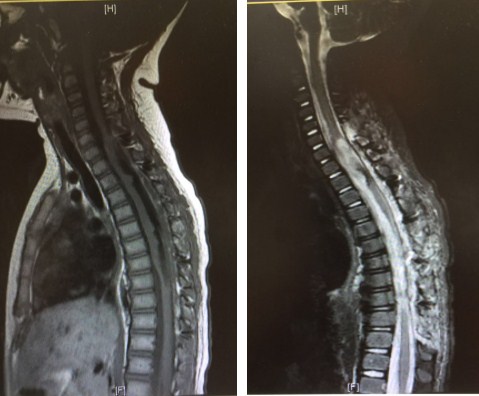

经过多方打听,然然的父母亲了解到北京清华长庚医院神经外科是专注于脊柱脊髓疾病治疗与研究的医疗团队,科主任王贵怀教授更是这一领域的专家,拥有二十多年手术治疗脊柱脊髓疾病的丰富经验,因此他们慕名来到了王教授的门诊。王贵怀主任热情接待了然然的父母亲。他仔细阅读了然然的脊髓MRI胶片,并认真的向夫妻俩分析和解释然然的病情:在然然脊髓的颈髓第6节段水平到胸髓第8节段水平长了一个长约10cm的髓内肿瘤,该节段脊髓明显增粗一倍,几乎挤满了这一位置的椎管内空间,而且肿瘤与脊髓之间看不到边界,根据王主任的经验,初步判定是室管膜瘤或者低级别的胶质瘤。从目前情况来看,手术是唯一的治疗方案。通过手术一来可以取到肿瘤样本进行病理检验,以明确其性质,为下一步是否放化疗提供依据,二来可以缓解脊髓受压的状况,释放这一位置的椎管内压力,一定程度上可以减轻脊髓的损伤。王主任还介绍说,从他多年来的手术体会和国内外学术文献的报道来看,MRI是间接影像,并不能完全反应病变的全部信息,不排除在肿瘤与脊髓之间有潜在界限的可能,如果那样的话,甚至有机会切除肿瘤。王主任的一番介绍,让迷茫中的然然父母看到了希望,他们带着然然办理了住院手续。

肿瘤与脊髓长度的对比

住院后,然然接受了一系列严格的检查,以评估她对这次重大手术的承受能力,所幸然然的各项指标均正常,这也坚定了大家的信心。但然然复查的MRI却让人揪心,图像显示,短短几个月时间,然然的肿瘤又长大了一点。王贵怀主任率领的神经外科团队在然然手术前进行了多次讨论,尽管肿瘤增大给手术增加了困难,但同时也激发了大家一定要战胜病魔,挽救然然的昂然斗志。

术后复查显示原肿瘤已近全切除,受压的脊髓有少许回弹